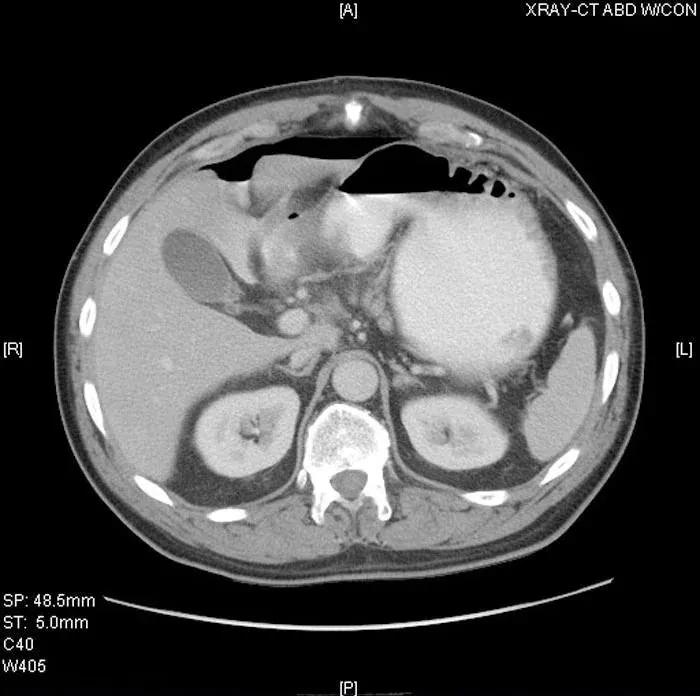

初始检查完成后,给患者注射额外剂量的静脉止痛药,可明显缓解部分疼痛(尽管上腹部的局部疼痛仍持续存在)。患者稍后做了腹部和骨盆的 CT 检查,并获得口腔和静脉造影图像(图 1 和图 2)。

图 1

图 2